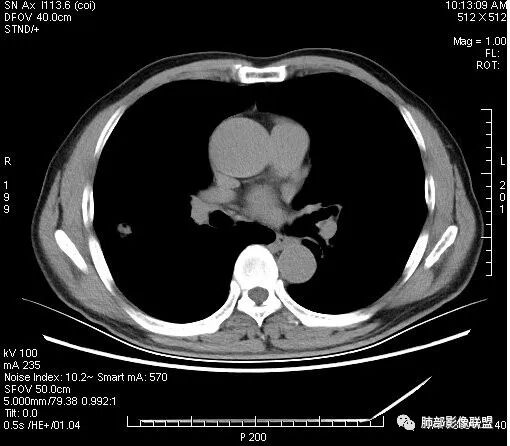

影像学改变:

1.右肺上叶后段类圆形结节影,密度不均,有坏死空洞,坏死比较彻底,内外壁都较清楚。

2.病灶有浅切迹,没有深分叶,毛刺大多细长且柔软。

3.可见棘状突起及胸膜牵拉,但未见胸膜凹陷。

什么意思?结节影有牵拉的动作,但似乎“出工不出力”,收缩力羸弱!

4.病灶轻到中度强化。病灶内血管走行较完好,病灶旁血管局部显示粗大。

5.支气管关系不确定。

6.灶周见小结节影(卫星灶),边界不甚清晰。